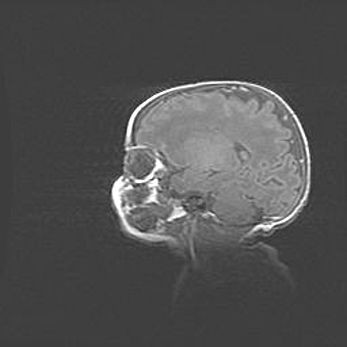

Множественные кисты обоих полушарий головного мозга, наибольшая из них в правой затылочной области. Ассиметричная атрофическая гидроцефалия.

Возраст: 7 месяцев

Вес: 5660 г

Пол: мужской

Окружность головы: 41,5 см

Срок гестации: 28-29 недель

Кисты головного мозга развиваются в результате многоочаговых некрозов вещества мозга и возникают вследствие перенесенной перинатальной инфекции, менингитов, энцефалитов, асфиксии, родовой травмы, расстройств мозгового кровообращения различного генеза. Образованию кист в веществе головного мозга плодов и новорожденных способствуют такие факторы, как высокое содержание в нем воды, недостаточная (или отсутствие) миелинизация и слабая астроглиальная реакция на повреждение.

Кисты могут сочетаться с гидроцефалией и другими поражениями головного мозга.